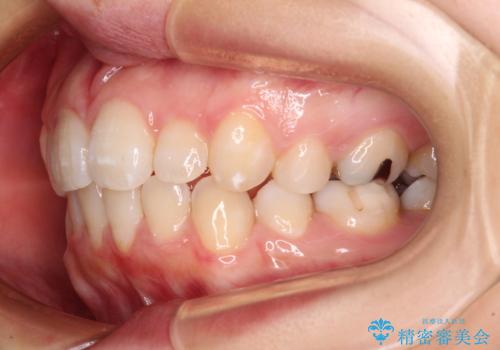

抜歯矯正の後戻り インビザライン・ライトによる矯正治療

- 矯正治療の後戻りを気にして来院された患者様です。

後戻りは軽微であったので、インビザライン・ライトにより矯正治療を行うこととしました。

治療途中、妊娠・出産があり、1年近く治療が停滞しましたが、無事に終了することができました。